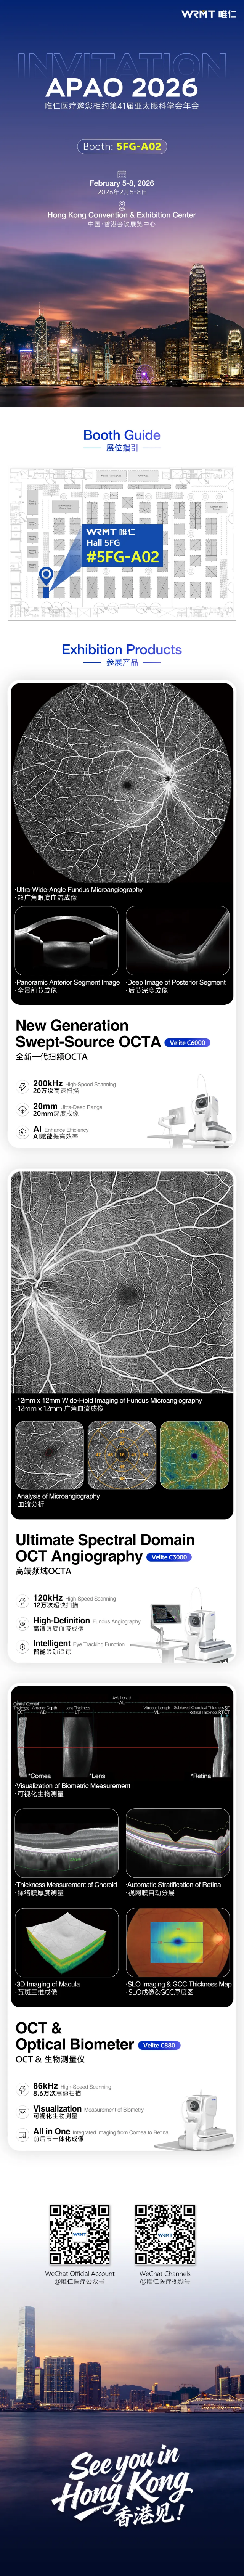

唯仁医疗邀您相约第41届亚太眼科学会年会(APAO 2026)